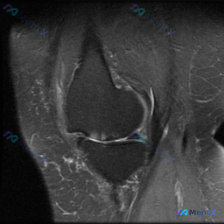

病例影像读片分享 整理了这张单膝关节冠状位T2加权脂肪抑制MRI,跟大家分享一下读片思路 影像基本信息 这是一张膝关节冠状位T2加权脂肪抑制序列MRI,图像对比度良好,能够清晰显示关节内软组织结构;左侧为膝关节外侧,右侧为内侧,本次显示层面包含股骨外侧髁、胫骨外侧平台及外侧关节间隙。 影像观察结果...